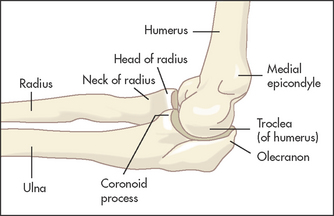

The humerus, radius and ulna meet at the elbow, which is a hinge and a pivot joint (see Figure 24.18). Pivoting occurs between the radius and ulna, and the articulation between all three bones forms a hinge joint.

Pain from the elbow is usually diffuse and may radiate down the forearm. It may occur over the lateral or medial epicondyle if the patient has tendinitis (tennis or golfer’s elbow). The patient may have noticed some swelling as a result of inflammation. Swelling over the back suggests olecranon bursitis. Stiffness may interfere with elbow movements and the patient may complain of difficulty combing the hair. When supination and pronation are affected the patient may complain of difficulty with carrying and holding. If the patient is aware of the elbow moving abnormally this suggests instability of the joint and may be a result of rheumatoid arthritis or trauma. Ulnar nerve trauma at the elbow may lead to a complaint of numbness or paraesthesias in the distribution of that nerve.

Look for a joint effusion, which appears as a swelling on either side of the olecranon. Discrete swellings over the olecranon or over the proximal subcutaneous border of the ulna may be due to rheumatoid nodules, gouty tophi, an enlarged olecranon bursa or, rarely, to other types of nodules (see List 24.5).

Feel for tenderness, particularly over the lateral and medial epicondyles, which may indicate tennis or golfer’s elbow, respectively. Palpate any discrete swellings. Rheumatoid nodules are quite hard, may be tender and are attached to underlying structures. Gouty tophi have a firm feeling and often appear yellow under the skin, but are sometimes difficult to distinguish from rheumatoid nodules. A fluid collection in the olecranon bursa is softly fluctuant and may be tender if inflammation is present. These collections are associated with rheumatoid arthritis and gout, but often occur independently of these diseases.